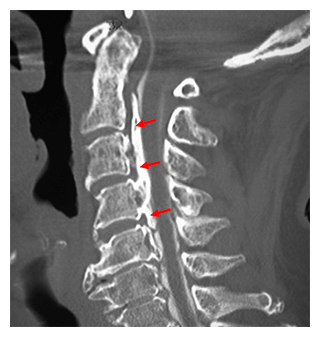

頚椎(背骨の首の部分)を側面から見た後縦靭帯骨化症のCT像(赤矢印は骨化した後縦靭帯)